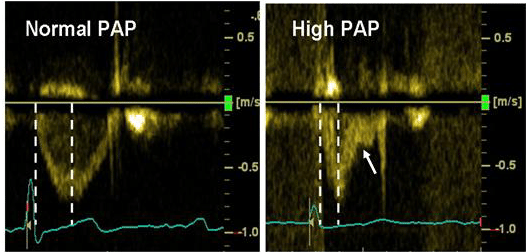

8/ Evidence suggests that in nearly 50% of cases PASP by doppler differs by >10 mmHg from RHC findings. Doppler in the RV outflow tract can help differentiate between PAH and group 2 PH as a mid-systolic notch on doppler indicates high PVR and poor PA compliance.